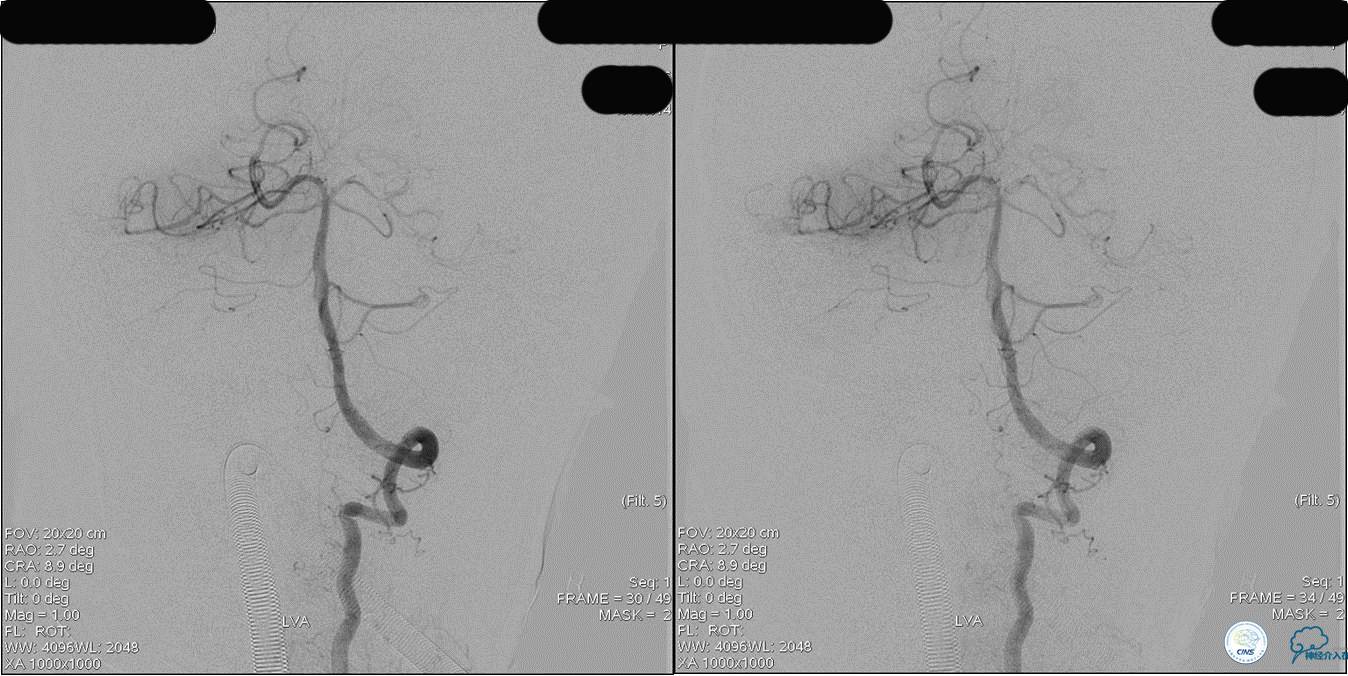

》DSA资料(左侧椎动脉)

》DSA资料(右侧椎动脉)

》DSA资料(经桡动脉,5F导引导管)

》DSA资料(前2次取栓,未取出,soli 4-20)

》DSA资料(第3次取栓)

第3次取出血栓

》DSA资料(第3次取栓后,发病10h)

》DSA资料(观察30min后,左椎造影)